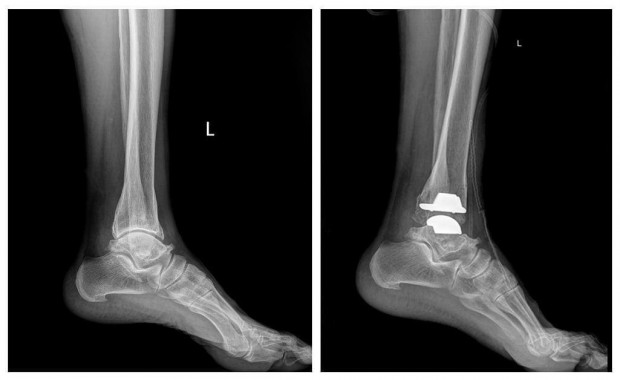

Гэмтэл согог судлалын үндэсний төвийн Насанд хүрэгсдийн мэс заслын тасгийн эмч, мэргэжилтнүүд шагайн хиймэл үе солих мэс засал эмчилгээг эх орондоо амжилттай нутагшууллаа.

ГССҮТ-ийн Насанд хүрэгсдийн мэс заслын тасгийн их эмч Ш.Баасансүрэнгээр ахлуулсан, тус тасгийн эрхлэгч Б.Баатаржав, Г.Бадамгарав нарын мэс заслын баг бүрэлдэхүүн шагайн үений хүнд хэлбэрийн артроз өөрчлөлтийн үед хиймэл үе суулгах мэс заслыг хийж, орчин үеийн дэвшилтэт мэс засал эмчилгээг тусламж үйлчилгээнд бүрэн нэвтрүүлээд байна.

Тус тасгийн хамт олон 2022 оны арваннэгдүгээр сард БНСУ-ын “Йонсей Гунвоо” эмнэлгийн захирал Eui Hyun Park болон бусад эмч, мэргэжилтнүүдтэй хамтран Монголд анх удаа шагайн хиймэл үе солих мэс заслыг хийсэн бөгөөд 2023 оны арванхоёрдугаар сараас эхлэн энэхүү мэс засал эмчилгээг бие даан амжилттай хийж буй юм.

Шагайн үений хүнд хэлбэрийн артроз өөрчлөлтийн үед хиймэл үе суулгах мэс заслыг Монголд нутагшуулснаар энэ төрлийн шалтгаант өвчлөл, зовиураар шаналж буй иргэд үйлчлүүлэгчид олон улсын стандартыг хангасан тусламж үйлчилгээг эх орондоо, бага зардлаар илүү хялбар, чанар хүртээмжтэй авах, амьдралын чанараа дээшлүүлэх зэрэг таатай боломж бүрдэж байна.